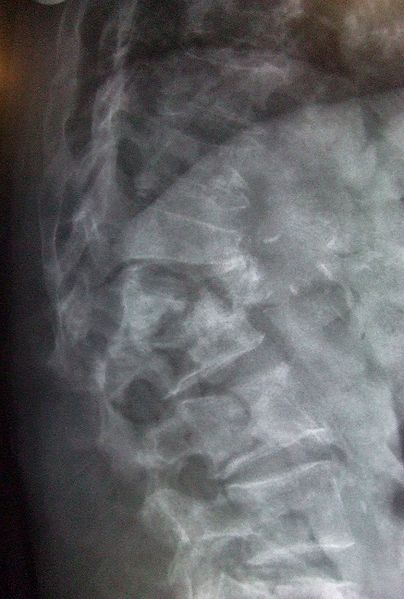

osteoporosisOsteoporosis is a metabolic disease in which bones become porous. Approximately 10 million Americans suffer from some from of this debilitating disease with symptoms including curvature of the spine and bone fractures. Although osteoporosis is often considered to be a disease of the elderly, steps to prevent it can be taken throughout life. Medical researchers have shown that osteoporosis results from an insufficiency of calcium during the growing years as well as later in life.